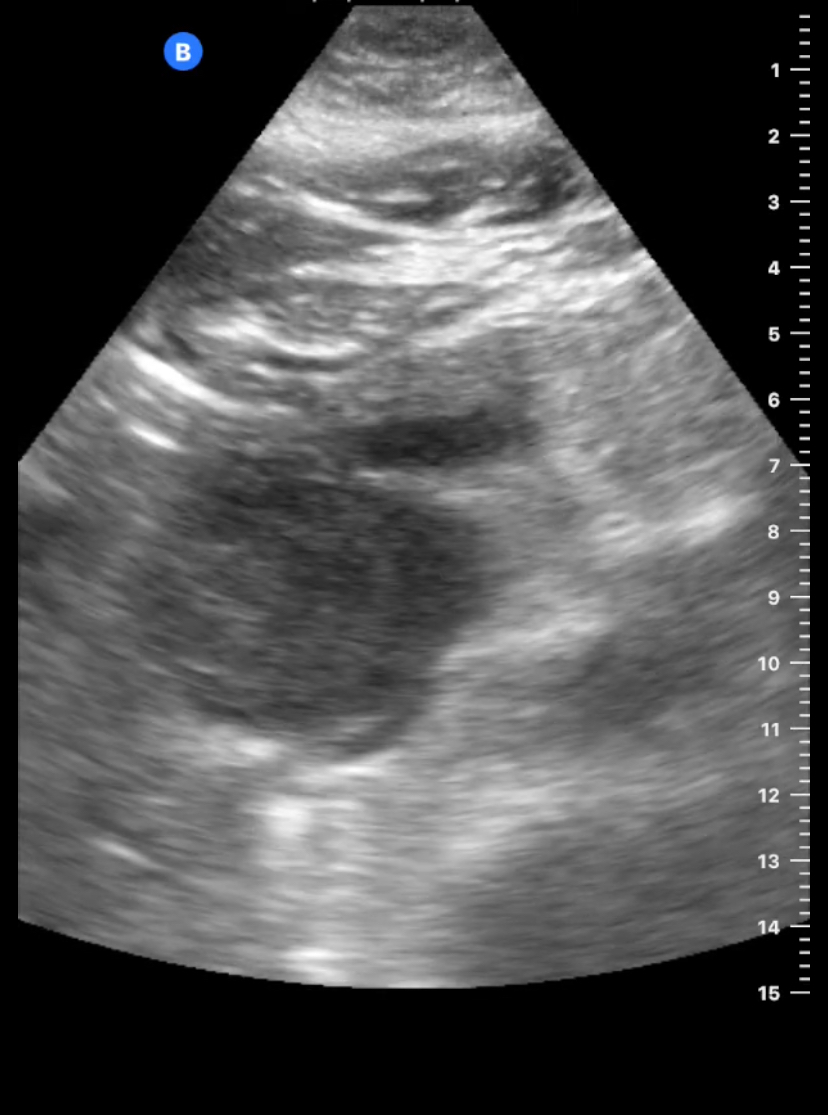

Paciente 2: vesícula distendida sin ecos en su interior, en línea media detectamos masa redondeada de 3-4 cm, Doppler positivo bajo proceso uncinado, dado dolor intenso no controlado se remite a urgencias e ingresa para estudio de posible masa pancreática.